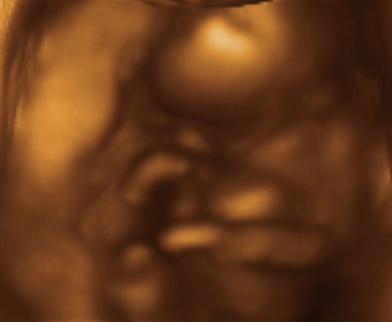

March 18 Update

Ultrasound today! We found out that it is indeed a girl...and that she should be here in mid August. She was REALLY shy, so these are the best pics we have...

Well, this proves it... the point of view is similar to the one you'd get if you sat the baby on a xerox machine and hit copy...

A good profile shot...